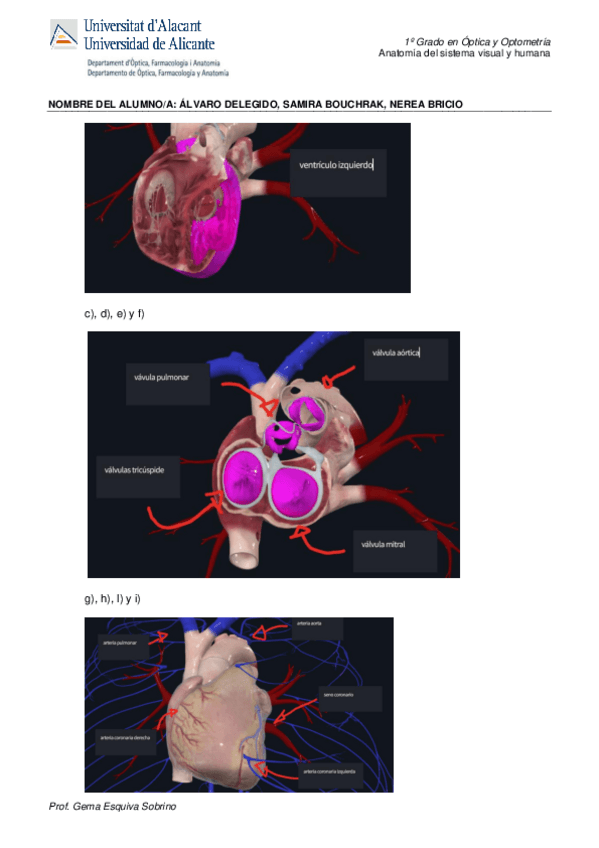

Practica-3.pdf

Practica-4.pdf